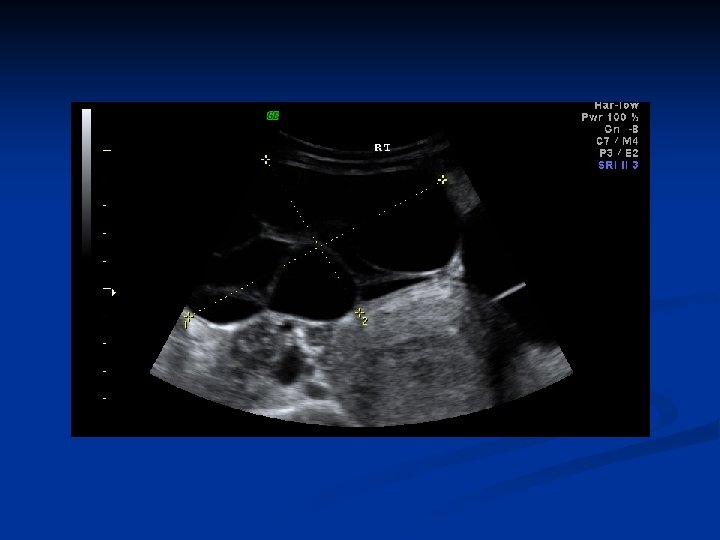

Leiomyoma Uteri n n n Benign neoplasm arising from smooth muscle cells in the uterine wall Pseudocapsule 20 -25% More commonly multiple Symptoms n n n Usually asymptomatic Metrorrhagia Menorrhagia Pain İnfertility

Leiomyoma Uteri n Etiology n n n Not known Unicellular in origin Estrogens are important in growth of myomas Progestins increases mitotic activity HPL may cause growth Classification n Submucous Intramural or interstitial Subserous

Leiomyoma Uteri n Clinical findings n n n Abnormal uterine bleeding 30% Pain Pressure effects n n Infertility n n n Intestinal obstruction Compress to ureters, bladder or rectum Pelvic venous compression Relationship is unknown 27 -40% of women with myomas are infertile Spontation abortion n 2 times more